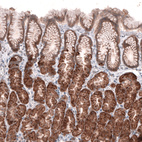

Immunohistochemical staining of human prostate shows moderate cytoplasmic positivity in glandular cells.